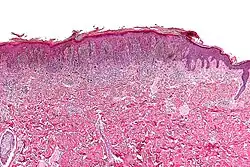

| Micrograph of a pigmented spindle cell nevus (top of image). H&E stain. | |

A pigmented spindle cell nevus is a skin condition characterized by a dark brown to black macule or papule, usually less than 6 mm.[1]